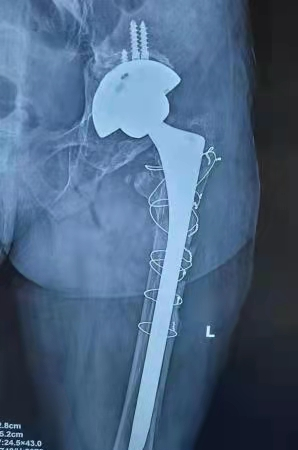

术后X线: